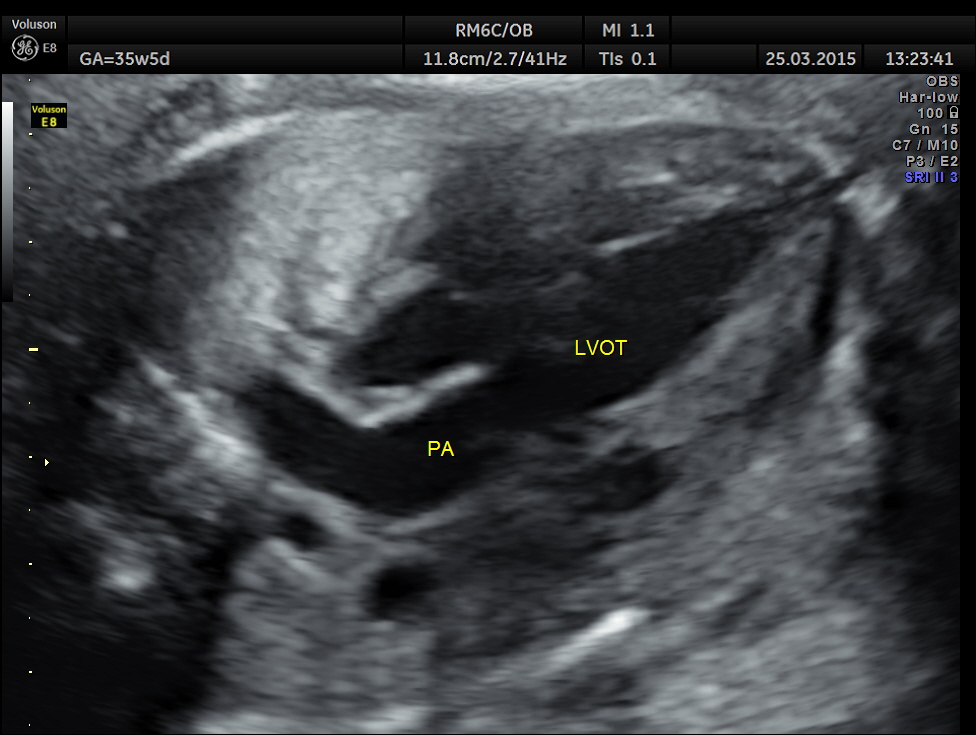

The artery coming out of left ventricle branches into two – suggestive of pulmonary artery.

The great artery arising from the LV branches into two suggestive of pulmonary artery.